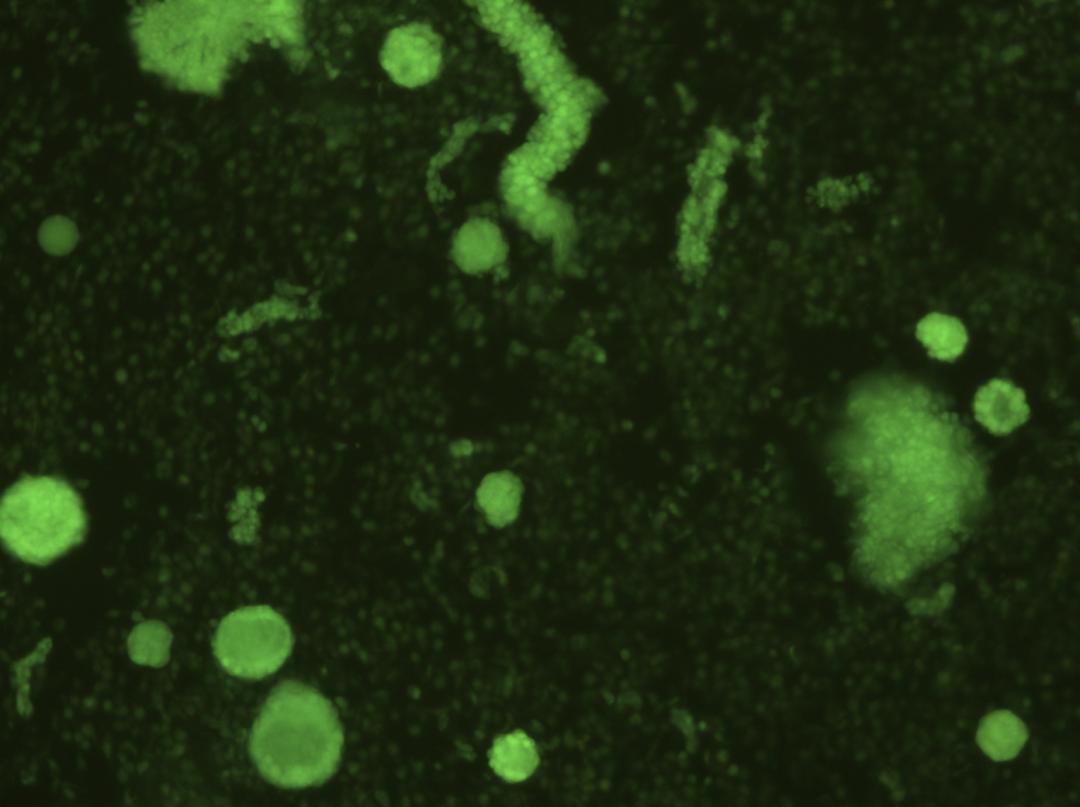

卵巢组织消化后在荧光显微镜下的典型图片

每一个圆形亮点代表一个卵泡

最终,卵巢库对这位子宫内膜癌患者成功进行了卵巢组织冻存,经卵巢组织活性检测,2mm直径的圆形卵巢组织含近100个卵细胞,冻存非常成功,估算为患者冻存了近6万个卵细胞,每个女性一生只有400~500个左右的卵细胞发育成熟与排出,这样的结果,标志着冻存了巨大潜力的生育与卵巢内分泌功能。预计可为此患者延长卵巢功能35年。